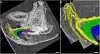

Flerfeltsbilde med fargekodet 3D-modell og gråtone-røntgen av klitoris og omkringliggende vev.

Det gule er dorsalnerven, som gir klitorishodet (i grått) følelse og dermed orgasmer. Det grønne er klitorisbeina og det lilla kalles klitorispærene. Dette er svamplignende legemer som svulmer opp og fylles med blod under seksuell stimulering. Det blå er nettverk av blodårer.

Sammensatte 3D-røntgenbilder av klitorishodet med fargekodede nerver og vevsstrukturer.

Når dorsalnerven når opp til klitorishodet, den delen av klitoris som er synlig over kjønnsleppene, forgreiner den seg som et tre. 3D-bildet viser frem store nervebunter i ulike farger. Den grå linjen markerer overflaten til klitorishodet. Det grønne området, markert CC, er toppen av klitorisbeina.